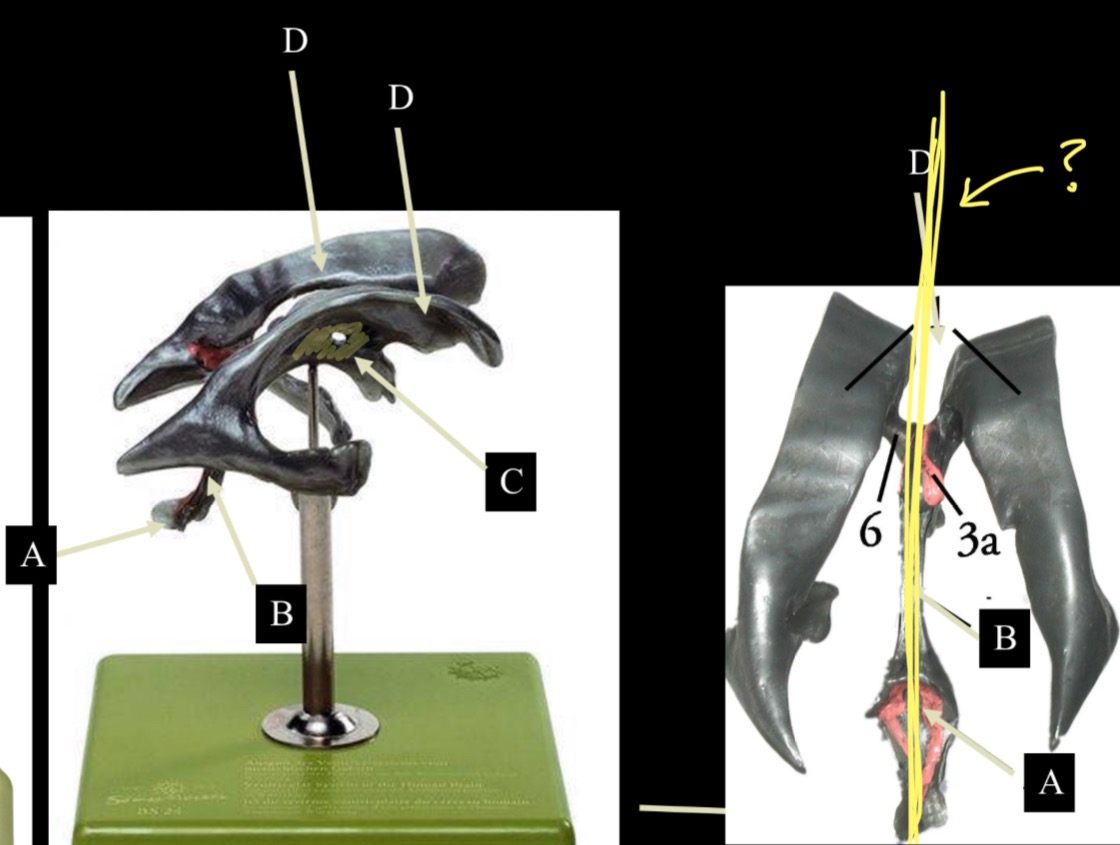

What is D?

lateral ventricle

Imagine thin membrane separating the 2 lateral ventricles

septum pellucidum

What is C?

3rd ventricle

What is B?

cerebral aqueduct

What is A?

4th ventricle

What is below A at the very end?

central canal (spinal cord)